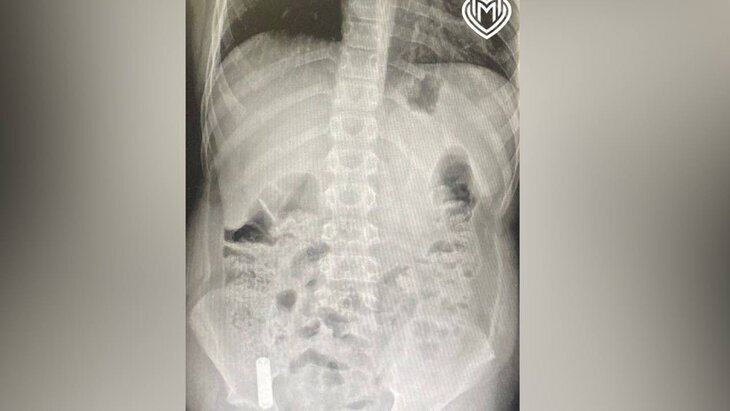

Фото: департамент здравоохранения Москвы

По итогам рентгеновского исследования медики обнаружили, что инородный предмет встал на уровне слепой кишки – в илеоцекальном углу. Было принято решение о проведении операции.